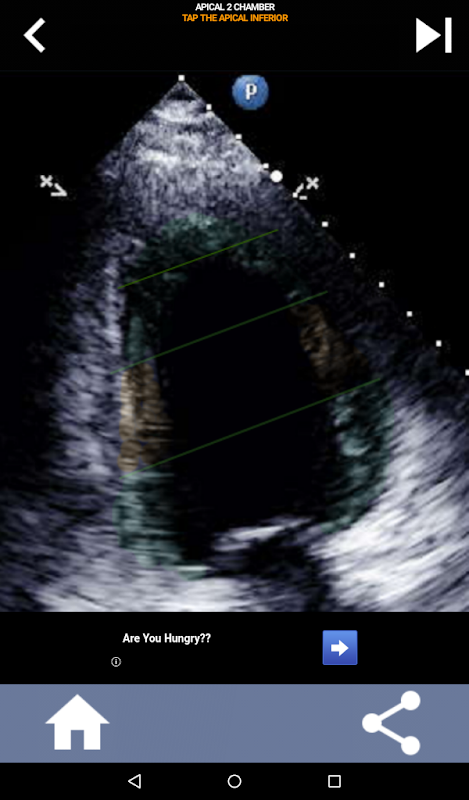

Enfoque visual basado en cuestionarios para aprender los segmentos cardíacos de la AHA: ecocardiografía

Esta aplicación pondrá a prueba su conocimiento utilizando imágenes de eco reales, que a menudo encuentro que es el mejor método de enseñanza.